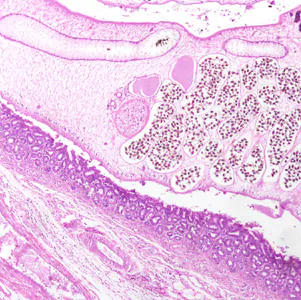

Several people developed gastrointestinal symptoms of watery diarrhea, nausea with vomiting, and low-grade fever approximately 1 week after attending a catered event. Stool specimens were collected for laboratory testing which included a formalin-ethyl acetate concentration with brightfield wet mount examination.